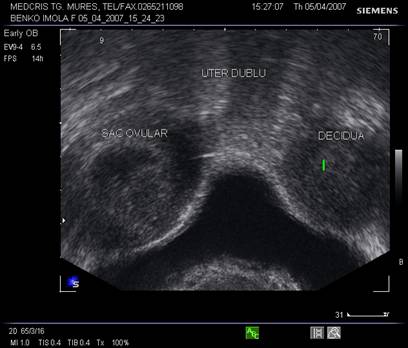

Sarcina va modifica aspectul ecografic al uterului malformat; in prezenta unui uter dublu, unul va contine un sac ovular, iar celalalt va avea un endometru ingrosat decidualizat.

Fig. nr. 101. Uter dublu cu un sac ovular intr-un corp uterin si endometru decidualizat in celalat corp, la ecografia vaginala in sectiune transversala